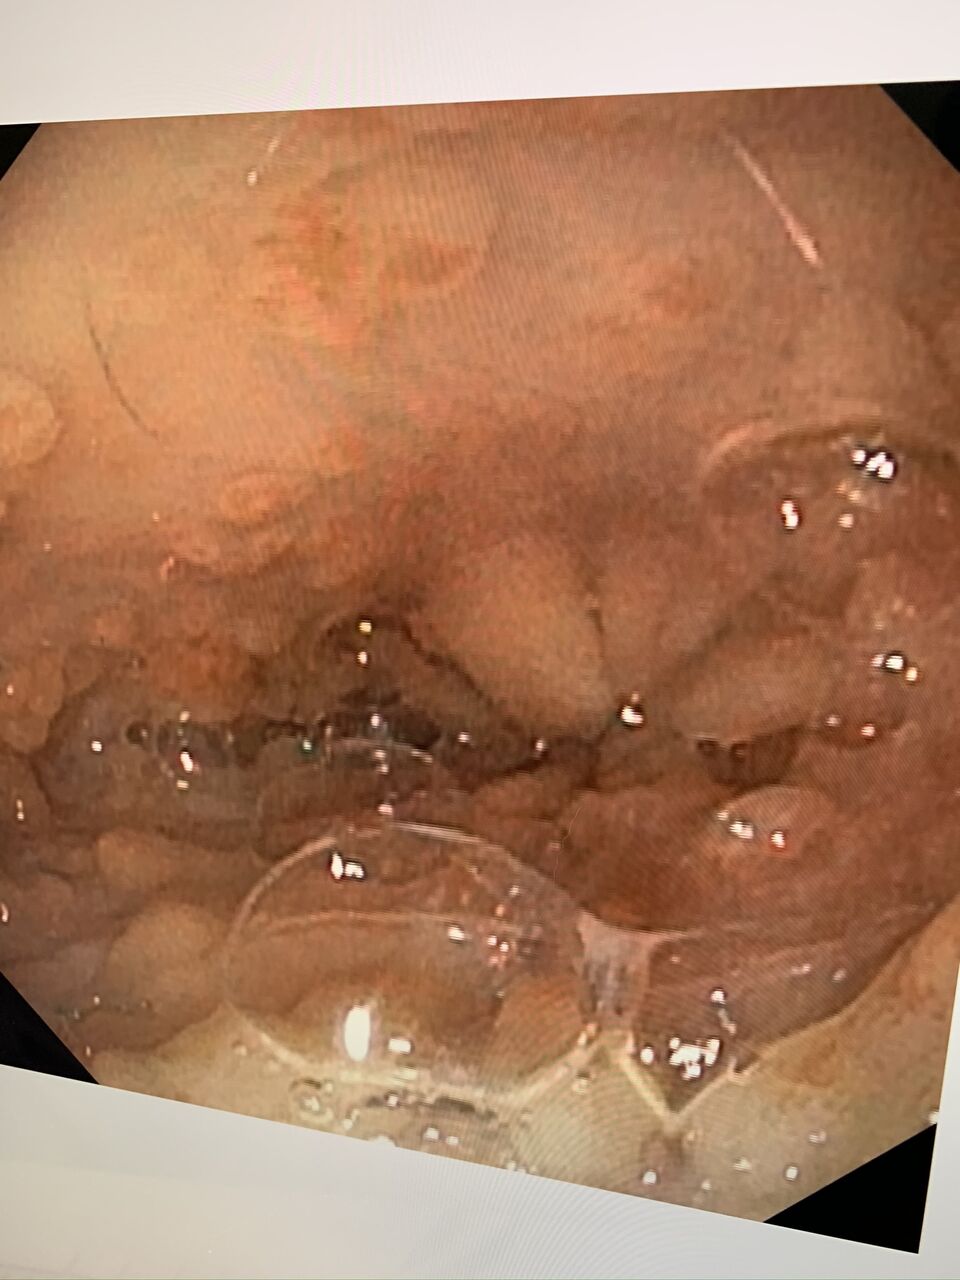

でも、微熱と言うか、40度ぐらいの熱が続くカカオは、若干、腹水もみられ、

最悪な事にFIPの診断が下されてしまいました。。。